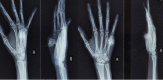

Case report: We have included five cases of osteochondromas occurring at rare locations with variable presentations and their management. We have included one case of metacarpal, one case of skull exostosis, two cases of scapula exostosis, and one case of fibula exostosis.